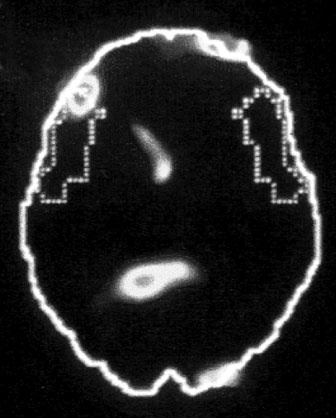

В. Зона Брока

Иллюстрация к книге — Тело помнит все [i_004.jpg]

Изображение мозга в процессе переживания травмы. Светлые пятна в лимбической коре (А) и зрительной коре (Б) соответствуют повышенной активности мозга в этих участках. На снимке (В) видна значительно пониженная активность речевого центра мозга.

Больше всего из полученных нами результатов нас поразила белая точка в левой фронтальной доле коры, так называемой зоне Брока. В данном случае изменение цвета означает значительный спад активности в этой области мозга.

Зона Брока – это один из речевых центров мозга, который зачастую бывает затронут у людей, перенесших инсульт, когда этот участок оказывается отрезан от кровотока. Без нормально функционирующей зоны Брока человек неспособен выражать словами свои мысли и чувства. Наши снимки показали, что при активации болезненных воспоминаний зона Брока отключалась.

Другими словами, перед нами было наглядное доказательство того, что последствия психологической травмы могут совпадать с последствиями физических повреждений, таких как инсульты, либо иметь с ними что-то общее.